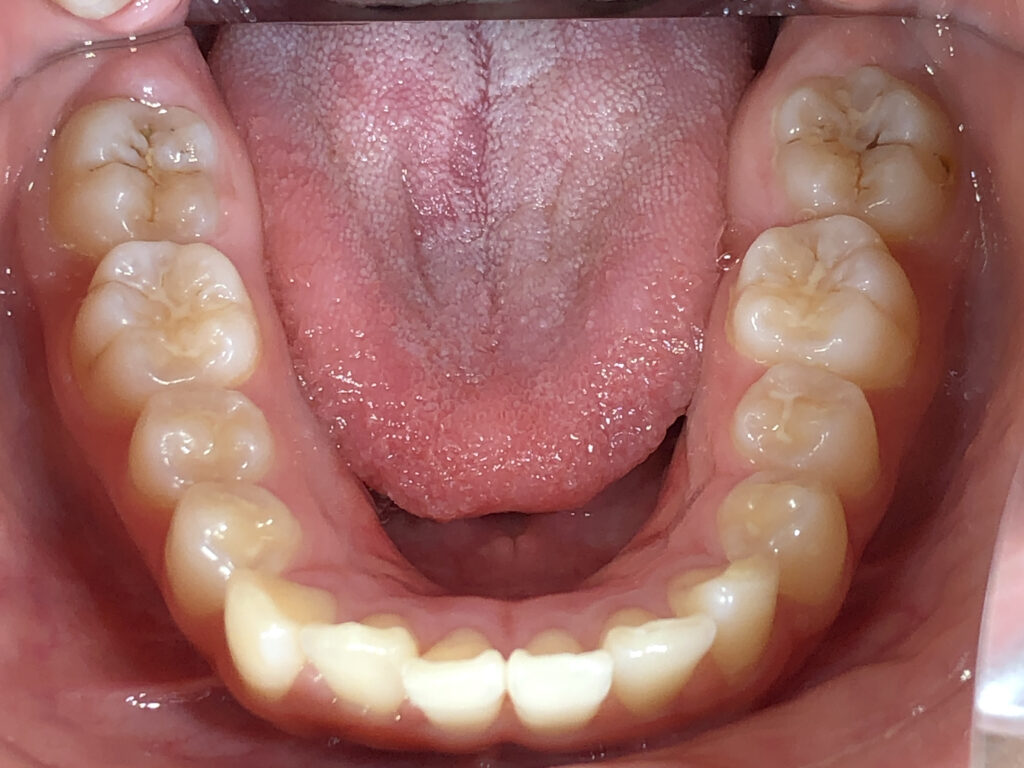

下顎

治療前